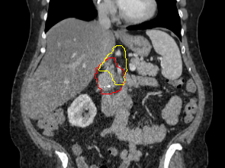

Image of a what is targeted with radiation. Red represents the pancreatic tumor, which is contacting with a major nearby artery. Yellow represents the Baltimore Triangle, which is now targeted in all patients, in addition to red volume. Credit: Amol Narang, M.D.

Using targeted radiation during surgery – referred to as intraoperative radiation – to eliminate pancreatic cancer cells that have spread to areas around the pancreas, investigators at Johns Hopkins have been able to reduce the recurrence rate around the pancreas to 5%. This is believed to be the lowest ever reported for this population of patients, according to a preliminary study by the team from the Johns Hopkins Kimmel Cancer Center.

The study enrolled 20 patients with borderline resectable or locally advanced pancreatic cancer. Patients received presurgical chemotherapy and radiation targeted to shrink the tumours away from the blood vessels. Then, during surgery to remove their tumours, patients received another dose of precisely targeted radiation using a robotic device that carries small radioactive beads inserted through catheters. The device enabled the team to pinpoint a triangular area near the pancreas, where recurrences commonly occur. Only one of the 20 patients experienced a recurrence around the pancreas at the 24-month mark – a major achievement for a cancer that, until recently, had lagged behind other cancers in treatment success.

The team learned that the pancreatic cancer cells were spreading along nerves near the pancreas to a fatty, nerve-dense triangular area just above the pancreas, which Narang calls the “Baltimore triangle.” When he and his colleagues started targeting the Baltimore triangle with radiation before surgery to kill these stray cancer cells, pancreatic cancer recurrence rates in their patients dropped from 47% to 12% at two years post-surgery. Yet, in the 12% who experienced recurrences around the pancreas, the recurrences continued to occur in the Baltimore triangle.

To further lower recurrence rates, Narang and his colleagues decided to deliver an additional round of Baltimore triangle-targeted radiation to patients during surgery after removal of the pancreatic tumour. He explained that, during the surgery, surgeons remove a part of the duodenum, next to the pancreas, making it easier to access the Baltimore triangle without risking harm to surrounding organs. The combination of radiation targeted to the Baltimore Triangle prior to surgery as well as intraoperative radiation to the triangle during surgery allowed Narang to deliver ablative doses of radiation to this region.

“The combination of intraoperative radiation and targeting the Baltimore triangle has gotten us to a 5% recurrence rate, which is the lowest-ever reported recurrence rate around the pancreas for this population of patients to our knowledge. But I think we can drop to 0% in our next study,” Narang says. “We must do whatever we can to prevent recurrences from happening, because when pancreatic cancer comes back, it is often incurable. These results give us hope, though, that this can be done for a cancer where even decade ago, most thought this wasn’t possible.”

The only recurrence in the study occurred in the part of the Baltimore triangle that the team had difficulty reaching during the intraoperative treatment. Currently, the team is developing strategies to target this hard-to-reach part of the triangle, with the hopes of reducing recurrences to zero. Once they’ve mastered that refined approach, they would like to team up with other cancer centres across the US to run a larger clinical trial to confirm their results.